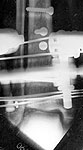

Please see images (shrunk as much as practical) below of a 22 year old man sent on to me 2 weeks after a climbing accident. Initial treatment in a plaster.

Treated by us with "minimal" internal fixation and application of a hybrid frame with 2 rings and wires around the metaphysis and 3 half pins in the diaphysis. Stable construct achieved. Tibial articular surface is well reconstructed-the lateral views are not included but show no articular steps or irregularity and the talus is well centred in the sagital plane.

Question is regarding the talus which had a lateral corner fracture as can be seen. This was a crush and was ungraftable. Now we can see some talar tilt and presumably this constitutes a risk factor for early OA. Are there any measures we could take? Ankle distraction? Limited weight-bearing for how long ? Other measures?